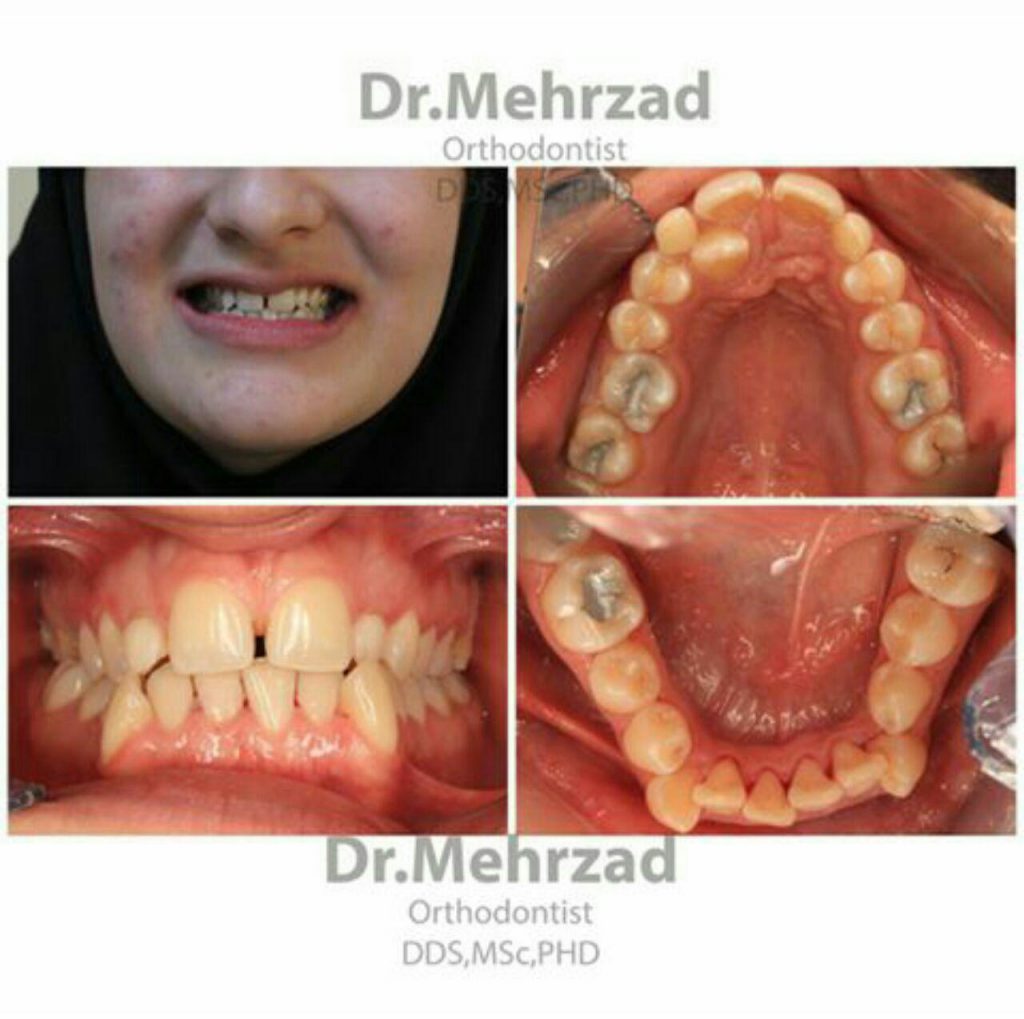

نامرتبی دندان ها

اگر دندان های شما شلوغ، کج یا در هم رفته باشند، یک متخصص ارتودنسی می تواند به صاف شدن و مرتب شدن آن ها کمک کند.

فاصله های زیاد بین دندان ها

وقتی دندان ها فاصله زیادی از هم دارند، ارتودنسی می تواند فاصله ها را کاهش داده و یک ردیف دندانی منظم ایجاد کند. برخی مواقع ممکن است ارتودنسی به تنهایی کافی باشد اما برخی اوقات میبایست همراه با درمان های دیگر مانند فرنکتومی هم باشد.